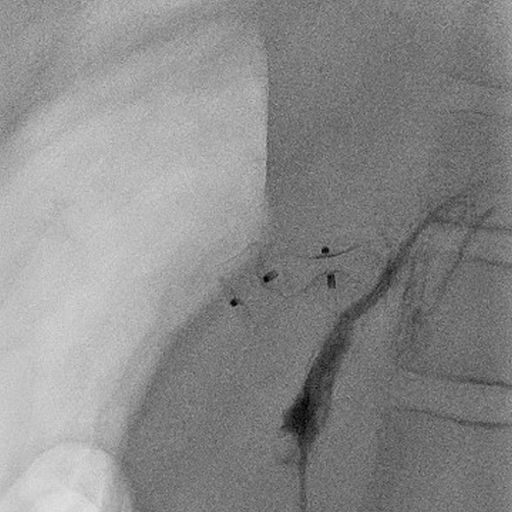

8 jähriger Junge nach Transplantation der linksseitigen Lebersegmente

In der Bildgebung (MRCP-Bild, A) zeigt sich eine Erweiterung der Gallenwege in der Leber, bedingt durch eine Engstelle an der Verbindung der Gallenwege (Gallenwegsanastomose). Entlastung der gestauten Gallenwege mittels PTCD. Punktion eines in der Leber gelegenen Gallenweges mit Hilfe von Ultraschall. Gabe von Kontrastmittel über die Punktionsnadel (B). Darstellung des gestauten Gangsystems und der Engstelle (Pfeil). Anschließende Anlage einer Ableitung (Drainage) zur Entlastung des Gallenwegssystems (C).